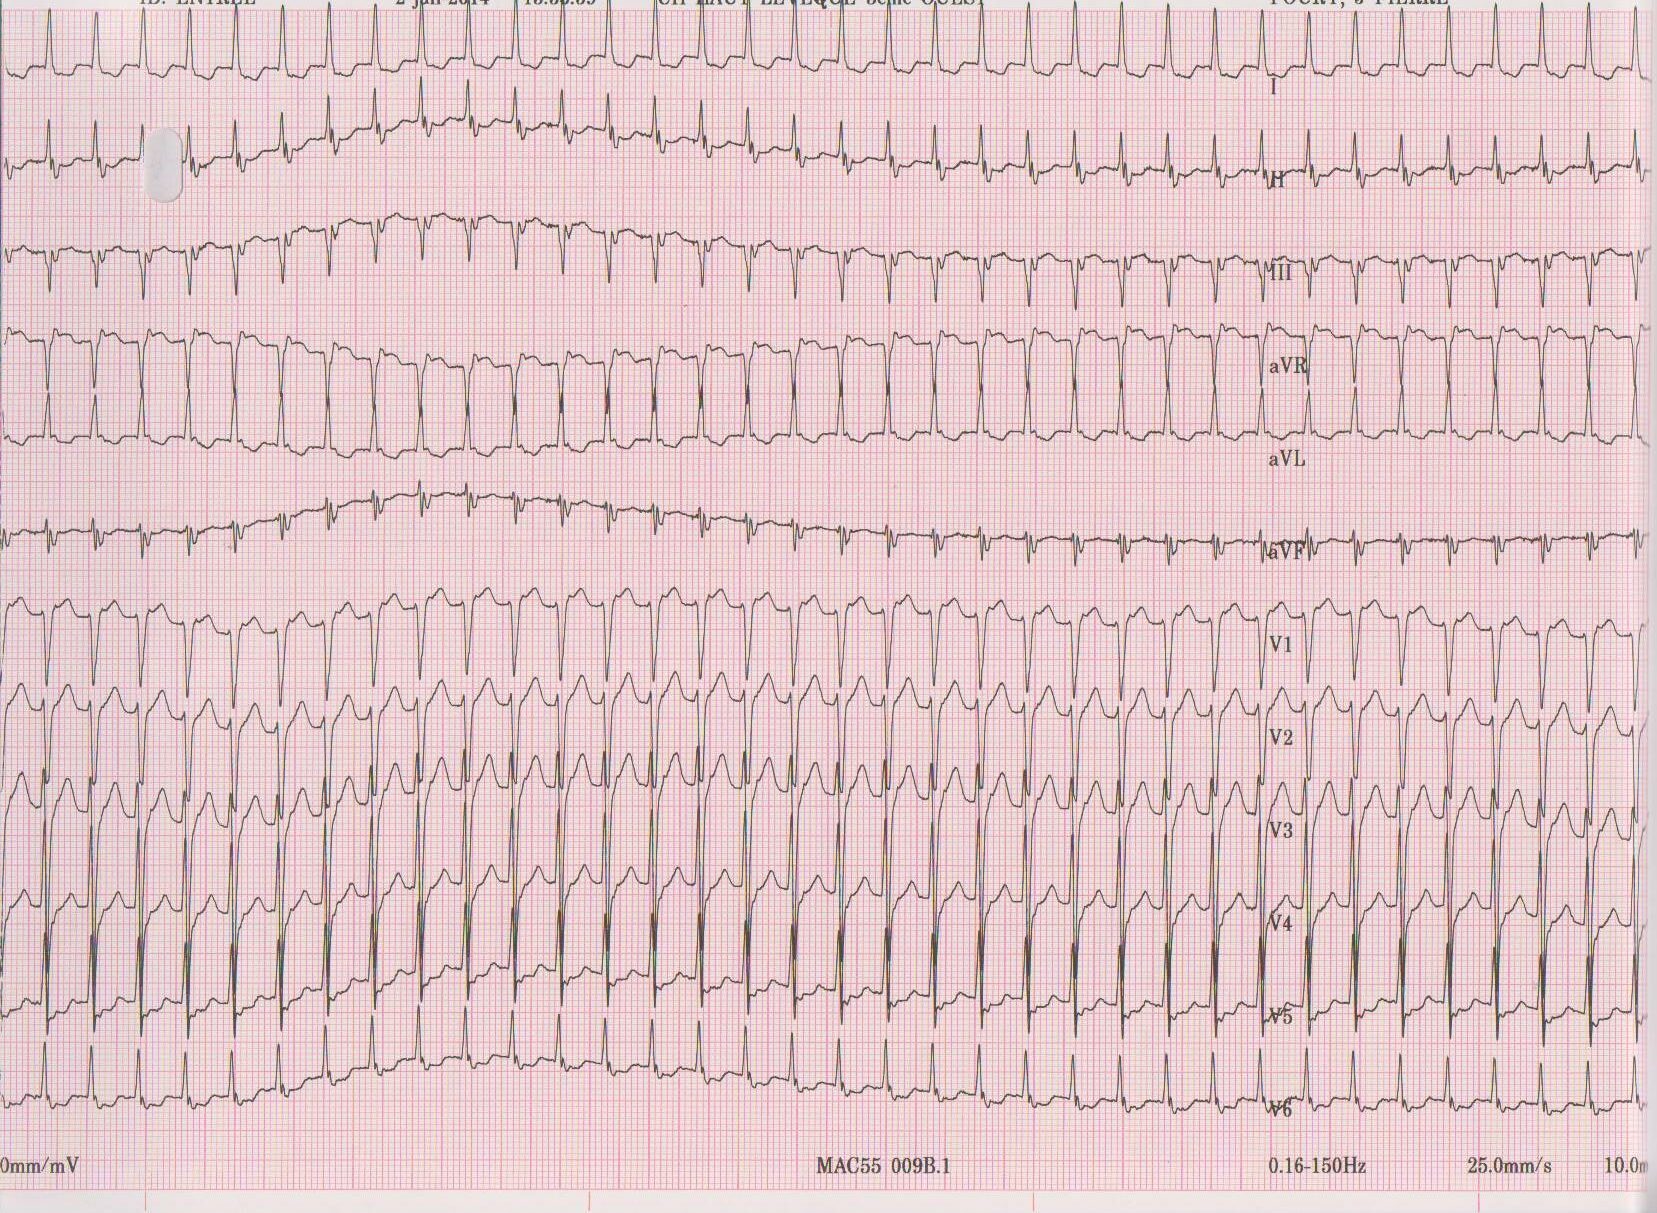

Description tracé

Arrêt de la tachycardie après injection d’une ampoule d’Isoptine; la modification de l’aspect du QRS sur les complexes d’origine sinusale confirme qu’il s’agissait bien d’une conduction atriale rétrograde;